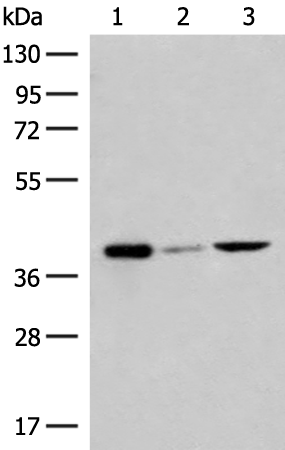

分类: 科研抗体货号: P06607别名: MTGM; MTGMP; C20orf52; bA353C18.2应用: WB,IHC反应种属: Human, Mouse